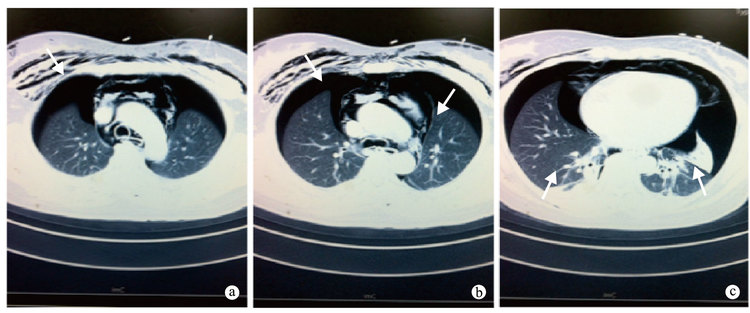

患者?女,41歲。因“惡心、嘔吐,吞咽困難2+年”于2014年5月16日入院。2+年前患者無明顯誘因出現惡心、嘔吐,嘔吐物為胃內容物,偶伴輕微吞咽困難;4+個月前患者受涼后惡心、嘔吐癥狀加重,伴食物反流,在當地醫院行食管鋇餐造影,考慮“賁門失弛緩癥”,未行氣囊擴張而轉診我院。入住我院后,經過患者及其家屬知情同意后,對患者實施經口內鏡食管肌切開術(POEM)。完善術前準備后,擇期氣管插管全身麻醉。術中應用T型海博刀從距門齒約30 cm食管處開窗,沿食管黏膜下層和環形肌之間間隙以T型海博刀潛行分離至賁門40 cm處建立黏膜下“隧道”,將距門齒30 cm至賁門10 cm食管環形肌束自上而下完全橫斷,止血后用鈦夾封閉“隧道”開口,隧道長度10 cm,肌肉切開長度10 cm,術畢賁門口開口明顯擴大。術后返回病房,患者訴胸痛明顯,伴氣緊。體格檢查:體溫、脈搏及心率正常,但呼吸稍急促,頸部及上胸部皮下捻發感明顯,指尖末梢血氧飽和度檢測為100%。考慮術后食管縱隔瘺。予安置心電監護,給予吸氧、禁飲禁食、埃索美拉唑抑酸、左氧氟沙星預防感染、卡絡磺鈉預防出血和靜脈營養支持治療。30 min后體格檢查:頸部及皮下氣腫明顯,雙肺呼吸音清晰,對稱存在,血氧飽和度正常。繼續觀察。30 min后患者訴氣緊加重,吸氣相明顯;體格檢查頸部明顯增粗,頸部及前胸皮下捻發感顯著增強,氣管居中,聽診雙肺呼吸音減低明顯但對稱。心電監護指尖血氧飽和度97%。急診行胸部CT示:食管下段管壁少許積氣,局部見致密金屬影,食管下段部分管壁欠連續;縱隔氣腫;雙側液氣胸,雙肺壓縮約35%雙肺下葉受壓不張(圖 1);掃及雙側腎周間隙、腎旁前間隙散在游離積氣;胸腹壁腫脹、皮下氣腫,雙肺散在斑片影及條索影,多系炎性病變,心臟未見增大。復測指尖末梢動脈血氧飽和度94%。密切監測生命體征及血氧飽和度,盡管患者仍訴胸悶,呼吸有憋感,但心電監護顯示患者生命體征平穩,血氧飽和度未再繼續下降。繼續保守治療,密切觀察病情變化。次日患者氣緊癥狀稍緩解,皮下氣腫無明顯減輕,3 d后皮下氣腫稍減輕,1周后患者皮下氣腫明顯消退,僅頸部皮下輕度捻發感。術后10 d好轉出院。

賁門失弛緩癥是一種原發性食管運動障礙性疾病[1],該病的病因及發病機制至今仍未明確,其治療多以緩解癥狀為主。主要治療方法包括藥物治療、內鏡下治療及外科手術治療。內鏡下治療因微創、迅速緩解癥狀成為該病治療的首選方法。內鏡下治療的方式包括:①氣囊擴張術;②肉毒素注射術;③可回收食管支架置入術;④POEM術。POEM是一種嶄新的治療賁門失弛緩的內鏡技術[2]。其原理是在內鏡器械及內鏡技術進步基礎上巧妙利用黏膜和肌層之間的空間建立黏膜下“隧道”,摒棄了以前的直接切開黏膜,其安全性及可行性可靠,已經公認為治療賁門失弛緩癥的優選方式。但其仍可能出現以下風險:①術中、術后出血;②食管穿孔、縱隔瘺、氣腹、氣胸;③胸腹痛;④胸腔或腹腔感染;⑤食管反流等。POEM技術于2008年發明[2],我國于2010年引進該技術[3]。故其并發癥的治療正處于探索階段。特別由于穿孔致氣胸、縱隔瘺、腹膜炎等是危險的并發癥。常規思維是術后需追加做開胸或開腹手術,但臨床經驗發現,術后追加外科手術可能會帶來更大的創傷。因為POEM術后的氣胸保守治療可能有效。嚴重的氣胸需要給予胸腔閉式引流。我國POEM診治指南特別指出:POEM術后氣胸在肺壓縮<30%時可以保守治療,若>30%應當給予安置胸腔閉式引流[4]。但我們的經驗卻發現,針對POEM術后的氣胸在雙肺壓縮<35%情況時,若無明顯的進一步惡化,在密切觀察情況下可以繼續內科藥物保守治療,無需外科開胸修補或者安置胸腔閉式引流術。這可極大減輕患者的身體痛苦亦可減輕患者的醫療費用。本例進一步說明POEM術后穿孔致氣胸保守治療是比較安全有效的方式。